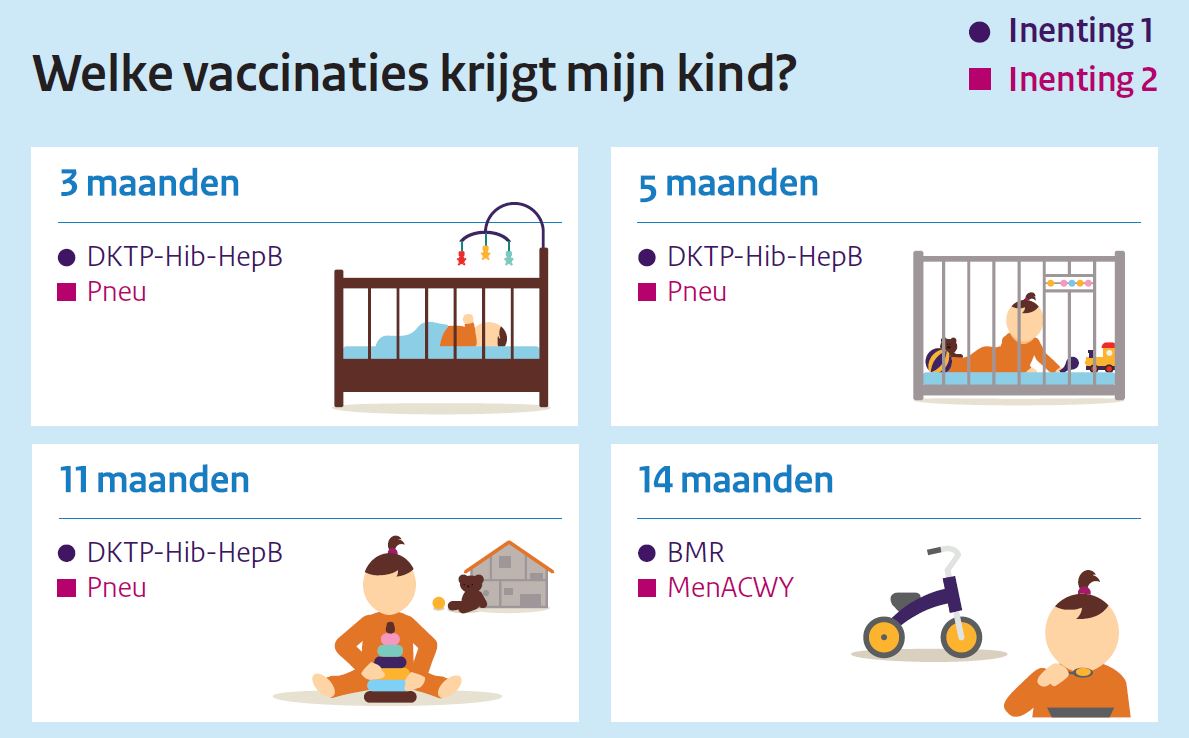

Vragen Antwoorden 22 Wekenprik Rijksvaccinatieprogramma Nl